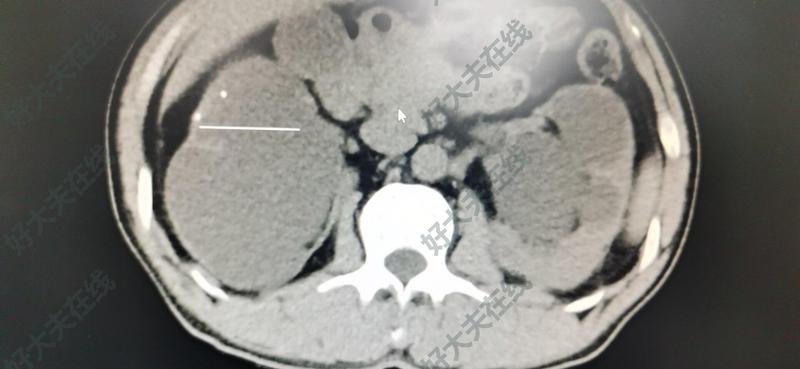

治療前 雙側(cè)輸尿管上段結(jié)石無明顯不適癥狀,就診時(shí)右腎皮質(zhì)菲薄,功能幾乎喪失,左腎重度積水。 治療中 完善相關(guān)檢查后,行雙側(cè)經(jīng)皮腎鏡一期碎石術(shù)。術(shù)后CT復(fù)查,右腎形態(tài)幾乎喪失,左腎仍有積水,可以慢慢恢復(fù)。 治療后 治療后7天 腎功能得以修復(fù),至少現(xiàn)在不會(huì)尿毒癥了。需要定期復(fù)查。防止結(jié)石復(fù)發(fā)。